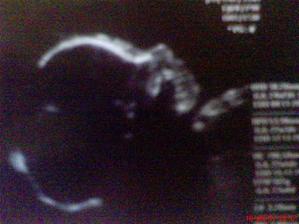

Mia II.cast(tehu)

nakolko maminka si zaznamenava skoro kazdy den mojho pobytu v brusku z vonkajsej strany,bolo potrebne otvorit novy fotoalbum;))tento sa zacina ukoncenim 32tt....